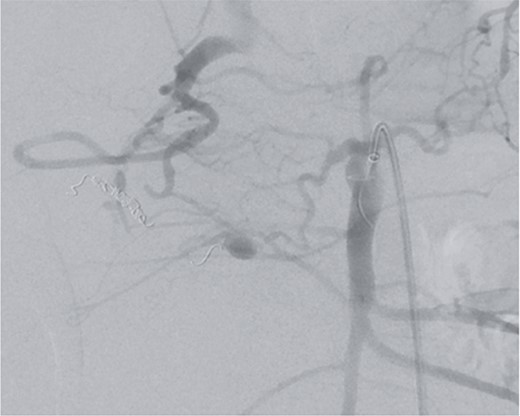

Postoperatively, the patient achieved hemodynamic stabilization in the intensive care unit. On the sixth postoperative day, there was a recurrence of circulatory collapse in addition to relevant bloody discharge through the drains. CT imaging once again revealed an active bleeding of the pancreaticoduodenal artery, which was successfully treated interventionally using coiling (Figs 2 and 3).

Angiography revealing the aneurysm of the pancreaticoduodenal arcade.

Postinterventional angiography, showing the aneurysm of the pancreaticoduodenal arcade, after interventional coiling.